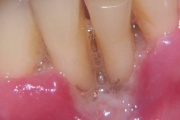

Lutipudelikaariese kahjustused

Lutipudelikaaries